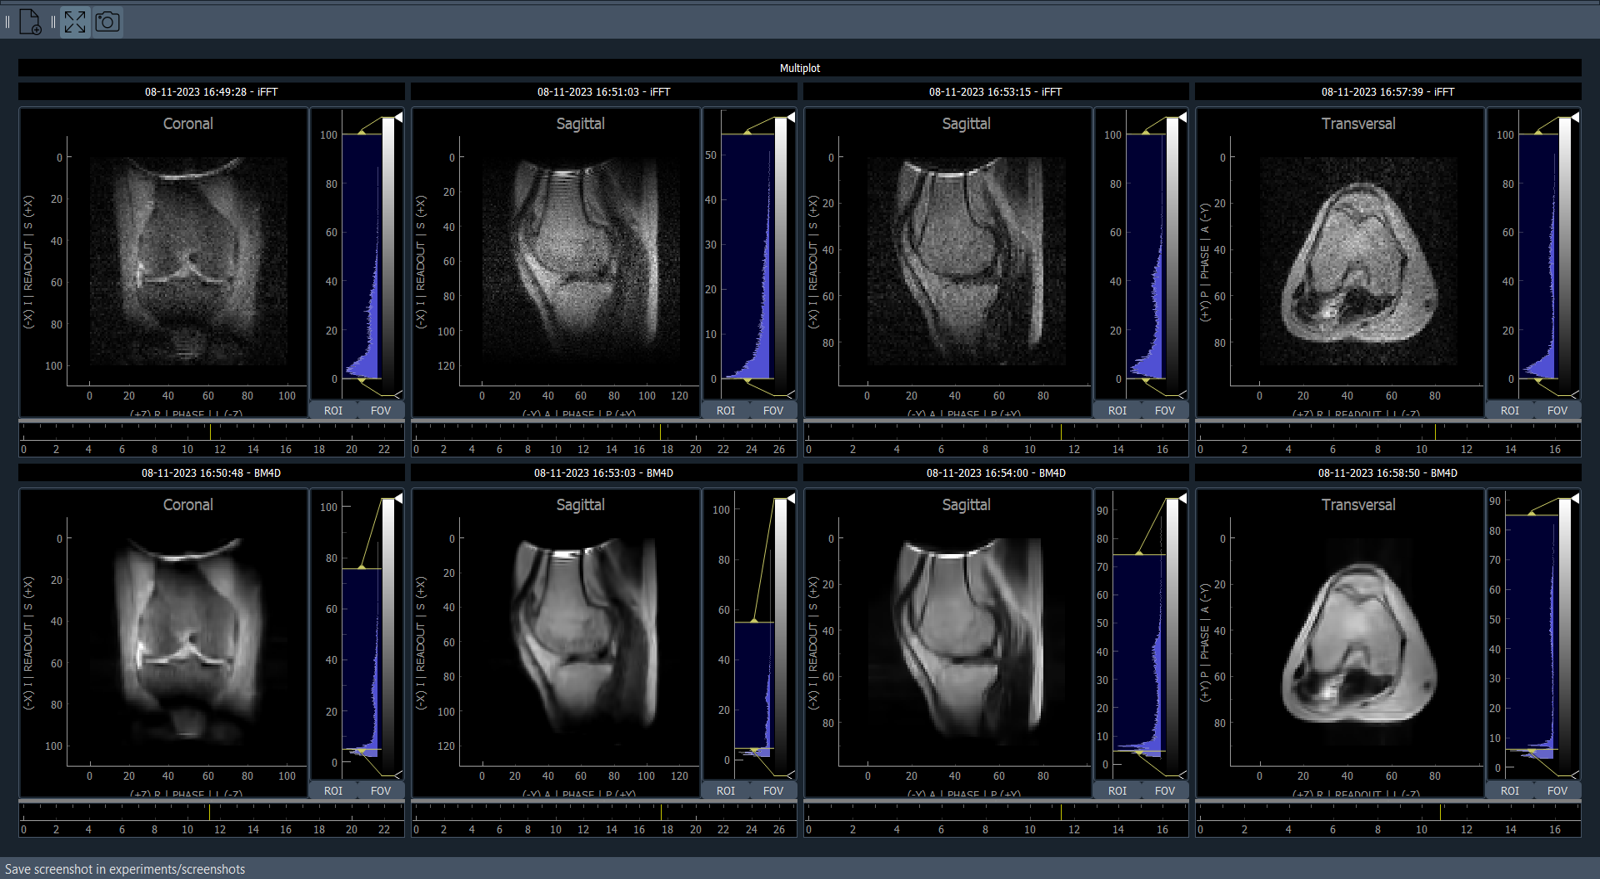

Following calibrations, we present the acquired and post-processed images in Fig. 7. From left to right, the four images correspond to coronal inversion recovery, sagittal T1, sagittal T2, and transversal T1. The top images are raw and post-processing in the bottom included only BM4D filtering, except for sagittal T1, where a cos-bell filter was applied in the k𝑘k-space readout direction to suppress artifacts observed in the raw image.

Refer to caption

Figure 7: Images resulting from the clinical protocol executed on the extremity scanner. From left to right: coronal inversion recovery, sagittal T1, sagittal T2, and transversal T1. Top (bottom) shows the raw (post-processed) images.